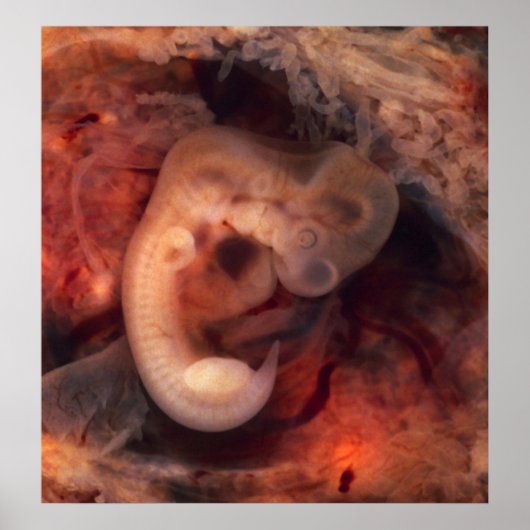

Humane embryo 7e week van de zwangerschap 5e week poster

Menselijk embryo (7e week zwangerschap, 5e week o.m.) Deze foto van een geopend eierstokje met een ectopische zwangerschap bevat een spectaculair goed bewaard embryo van 10 millimeter. Het is ongebruikelijk om embryo's in een ectopie te zien, en het is nogal ongebruikelijk dat men dit goed in stand houdt (en niet verstoord wordt door het mes van de prosector). Zelfs een embryo dit kleine show heeft zeer verschillende anatomische eigenschappen, zoals staart, ledematen, hart (dat eigenlijk uitsteekt uit de borst), oogbekertjes, cornea/lens, hersenen, en opvallende segmentatie in somites. De draagtas is omringd door een heleboel chorionische villi die op langwerpige partijballonnen lijken. Dit embryo is ongeveer vijf weken oud (of zeven weken in het biologisch misleidende maar uiterst praktische datingsysteem dat in de verloskunde wordt gebruikt). Schrijf u in voor de heer Rebates voor het VRIJE en bespaar 12% op elke zazzle bestelling, bovenop een inschrijvingsbonus van 5,00 dollar Alle rechten voorbehouden; zonder vooroordelen, verhaal of kennisgeving (U.C. 1-308) http://en.wikipedia.org/wiki/File:Tubal_Pregnancy_with_embryo.jpg. embryo zwangere vrouwen baby "menselijk embryo".